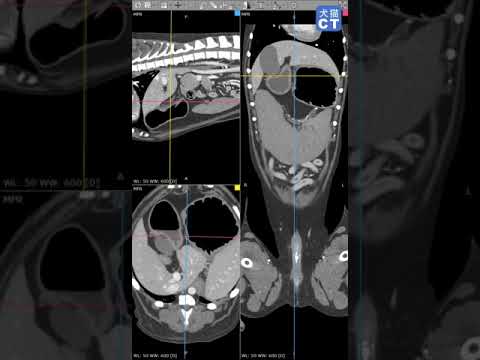

犬のインスリノーマの診断

犬のインスリノーマの診断は、次の点に基づいて行う必要があります。

- 臨床病歴と身体的調査: すでに述べたように、この病状を患う犬は主に持続的な低血糖に関連した臨床症状を示します。

- 血液検査(血球計算および生化学):犬のインスリノーマの最も指標的なパラメーターは、腫瘍細胞による過剰なインスリン産生による空腹時低血糖状態(値が60 mg/dl未満)の検出です。ただし、低血糖を確認するには、単独で測定するだけでは十分ではなく、8 時間の絶食期間中、1 時間ごとに測定して曲線を作成する必要があります。

- 病理組織学的分析: 腫瘍の切除時に行われ、診断を確認できます。顕微鏡的に見ると、膵臓細胞腫瘍はよく分化した細胞によって形成され、有糸分裂はほとんどありませんが転移しやすいものです。